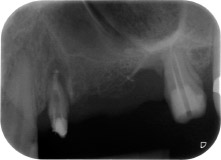

apical periodontal lesion at tooth 24

Fig. 1: 58-year-old patient. Preoperative radiograph showing an apical periodontal lesion at tooth 24 and horizontal loss of alveolar bone in the second quadrant.

A 58-year-old female patient complained of pain and increased mobility of her bridge abutment tooth 24. Periodontal inflammation was present with pocket depths of 7 mm mesiobuccally and more than 12 mm distally, as well as third-degree furcation involvement. Moreover, the radiograph revealed an extensive periodontal lesion around the apical region of the (alio loco) endodontically pretreated tooth 24 (Fig. 1).

One month later, on the day of surgery, pain and inflammation at tooth 24 were minimal, but mobility of Miller class 2 was still present. After opening the flaps and cleaning the periapical and peri radicular infected tissue, the extent of the bone defect became obvious (Figs. 2 and 3).

At the buccal root, all vestibular and distal bone was missing. Attachment was essentially restricted to the palatal root, underlining the preliminary poor prognosis. Tooth 27 also showed a reduced horizontal attachment and a minimal apical rarefaction (cf. Fig. 1) without clinical symptoms.